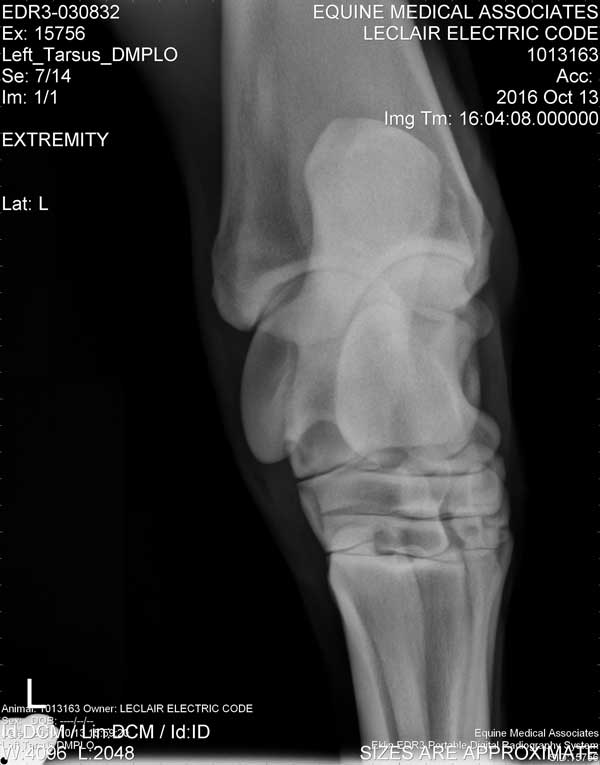

Electric Code is 11 years old at the time these X-Rays were taken on October 13, 2016

Hock/Tarsal

Left